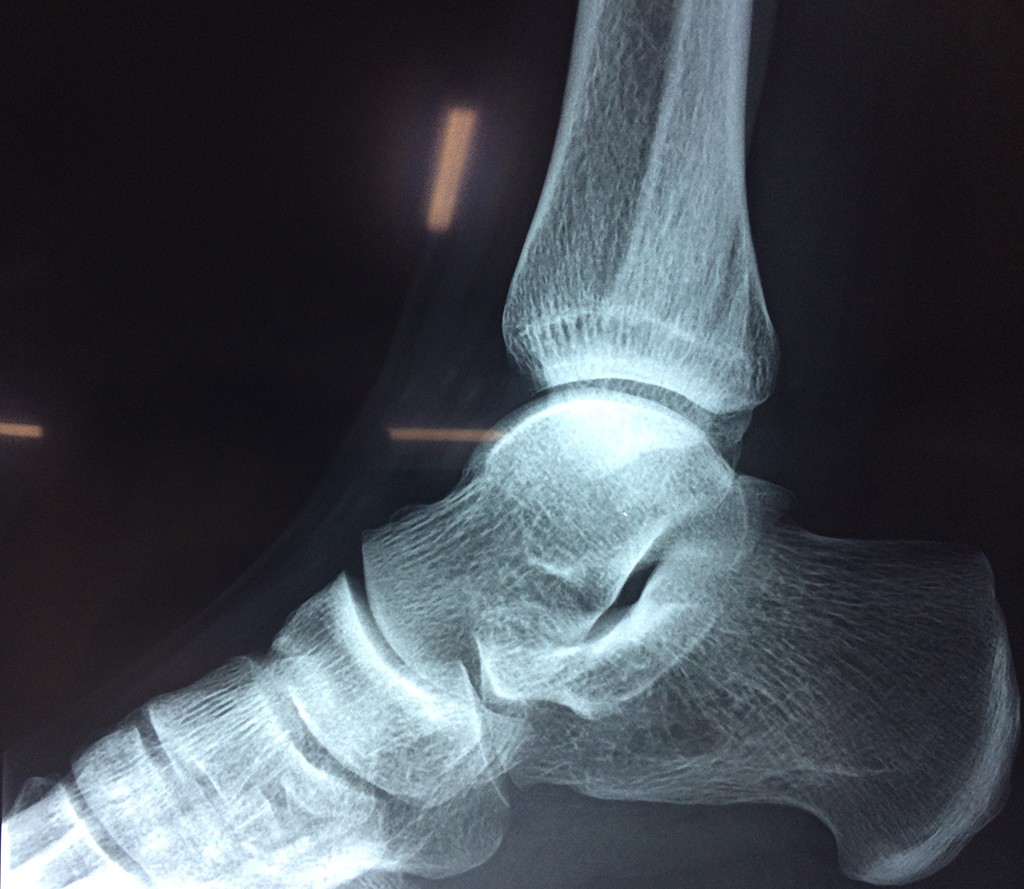

Calcaneo - Tobillos

Una fractura de tobillo es la rotura de uno o más de los huesos del tobillo. Estas fracturas pueden ser:

Algunas fracturas de tobillo pueden requerir cirugía si:

- Los extremos de los huesos están desalineados entre sí (desplazados).

- La fractura se extiende hasta la articulación del tobillo (fractura intra-articular).

Cuando se necesita cirugía, es probable que esta implique el uso de clavijas de metal, tornillos o placas para sostener los huesos en su lugar mientras la fractura se consolida. Los elementos de soporte pueden ser temporales o permanentes.